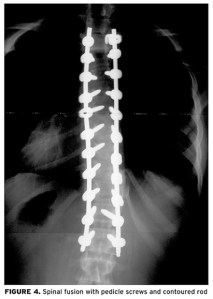

Large curves (those between 20-40 degrees) will require bracing to prevent further progression of the curve. If vital organs are compromised, surgery is even possible, but usually not until angles of 45 degrees or greater are found. (Below is an x-ray of a surgical correction using contoured Harrington rods and pedicle screws.)